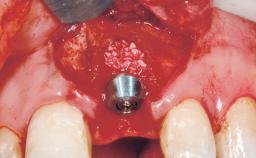

Late Flapless Placement of an Implant in a Maxillary Left Central Incisor Site

A 39-year-old male patient presented with a chief complaint of discomfort and gingival discoloration around his maxillary left central incisor. He was in good general health and was a non-smoker. His past dental history was significant because of the traumatic fracture of tooth 21 in a sporting accident at age 13. Initial dental treatment included endodontic therapy and a full-coverage restoration. The patient became symptomatic 5 years later, when structural failure of the tooth resulted in the dislodgment of the crown. Endodontic retreatment, apical surgery, and post-and-core restoration were performed.

Type of Implants One-Piece

Bone Augmentation Horizontal|Staged

Augmentation Materials Xenogenous|Membrane

Bone Volume Deficient horizontally, requiring prior grafting